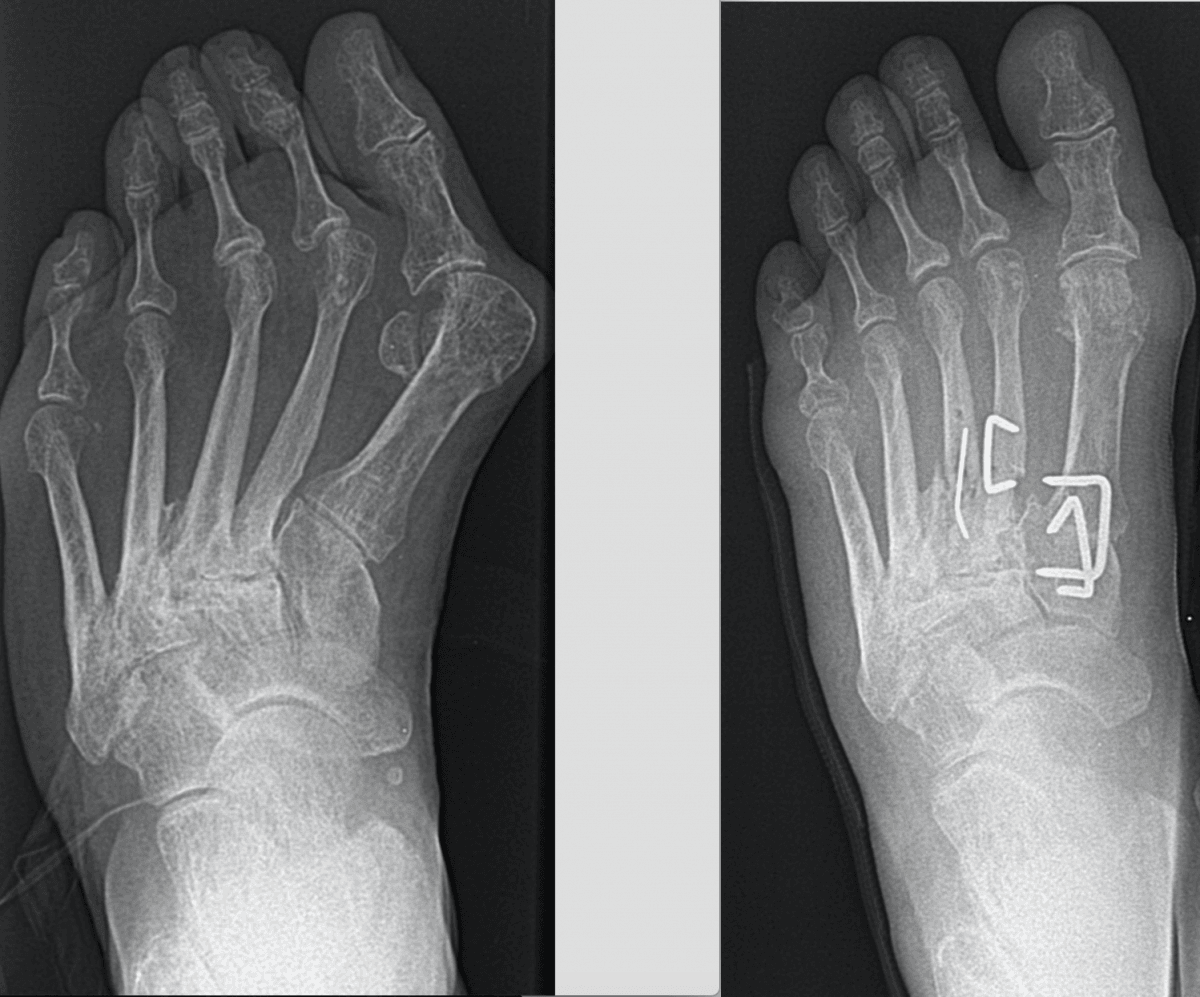

pt01hallux3 0